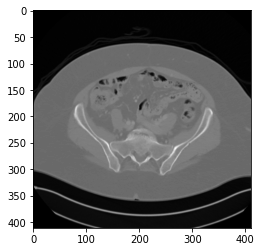

原始图像中的一个片段: